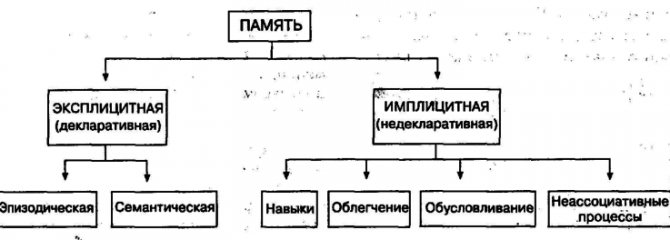

Довготривала (декларативна) пам’ять може вміщати безмежну кількість інформації, яка здатна зберігатися все життя. Цей вид пам’яті утримує смислове (подієву) складову отриманих відомостей. Вона поділяється на:

- семантичну – вид пам’яті, який містить загальну інформацію про найбільш важливі поняття, події (відомості про навколишній світ, рослинах, тварин і т.п.). Така пам’ять «локалізується» в нижневисочной корі;

- епізодичну – вид пам’яті, що містить відомості з особистого досвіду людини, які прив’язані до певних людей, подій, місць і т.п. Зберігається така інформація завдяки лімбічної системи головного мозку.

Також виділяється процедурна пам’ять, яка забезпечує несвідоме формування рухових та інтелектуальних навичок і «знаходиться» в області базальних гангліїв.